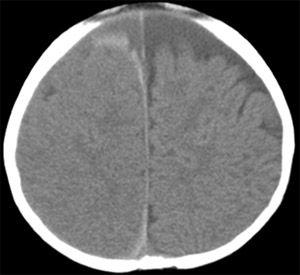

By the time these results were returned, a large hematoma was noted at the site of the blood draw. The infant’s condition was changing rapidly and a CT scan of the head was ordered. The scan revealed a large left parietal intraparenchymal hemorrhage (Figure). Edema was noted and a midline shift, with no herniation.